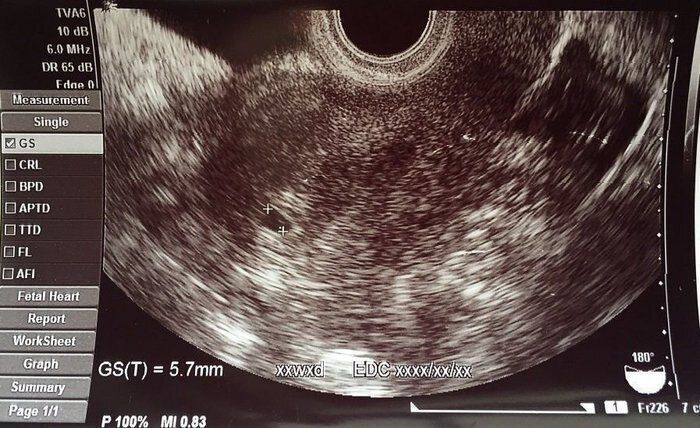

はやしなおさんの妊娠4週目のエコー写真 正常な位置に胎嚢を確認

生理予定日にフライングで妊娠検査薬で検査。結果はうっすら陽性。そこから約1週間の間に2度検査薬で妊娠を確認。待ちに待った2人目妊娠を日に日に確信しました。妊娠4週目で産婦人科へ。胎嚢5.7mmと想像よりだいぶ小さく、まだ安心はできないと自分を落ち着かせたのを思い出します。なるべくいつも通りに生活をしようと心がけました。